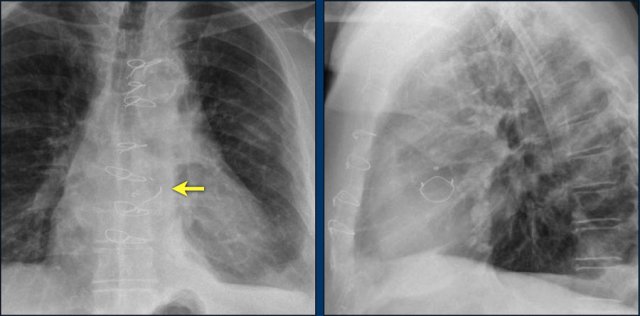

First study the images.

Then continue reading.

The findings are:

• Two epicardial leads connected to pacemaker

• ICD

• two leads to right ventricular apex

• one lead contains two shock coils

• tricuspid valve (arrows)

• mitral valve